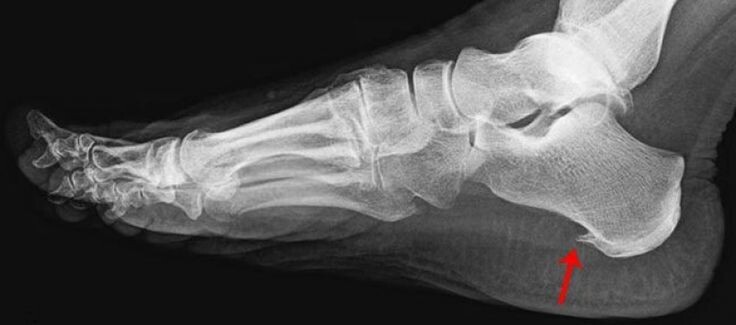

Главным методом диагностики этой проблемы является рентгенография, на которой определяется костный вырост и его размеры. Иногда признаки воспаления и утолщения подошвенного апоневроза определяются при ультразвуковом исследование стопы. А вот на выполнение МРТ стопы деньги можете не тратить.

Рентгенологическая картина пяточной шпоры